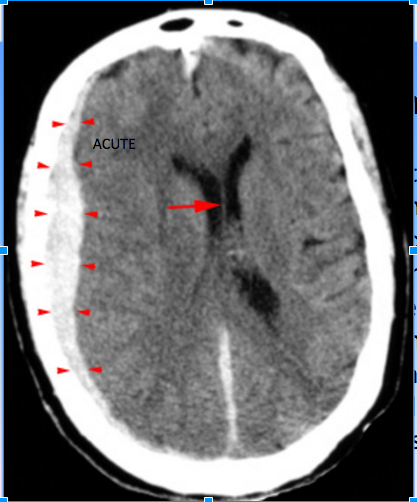

Subdural Hematoma CT has the following characteristics: 3

High density, crescent shaped hematoma (arrowheads)

overlying the right cerebral hemisphere. Whats important to note in this image?